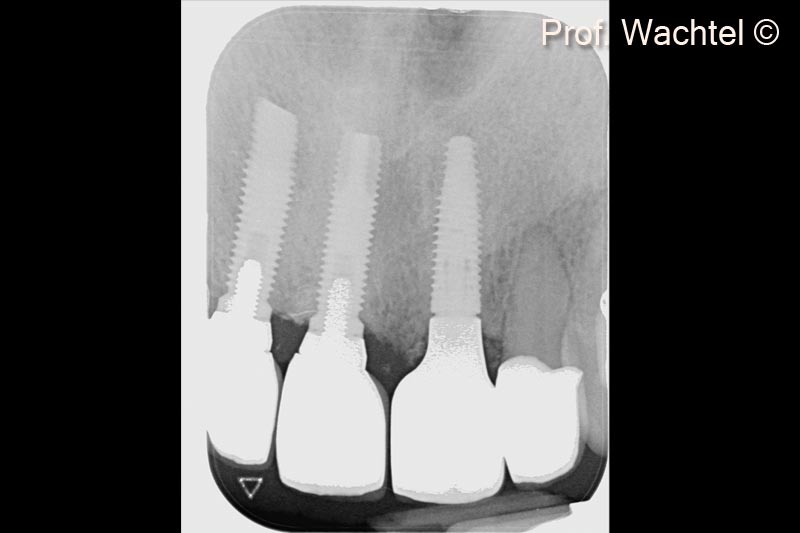

5. X-ray of the 3 implants: #12 and #11 18 years old - #21 implantation site is prepared according to the Multi-Layer Technique (MLT)